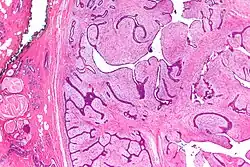

Micrograph of a phyllodes tumor (right of image) with the characteristic long clefts and myxoid cellular stroma. Normal breast and fibrocystic change are also seen (left of image). H&E stain.

Phullon means 'leaf' in Greek. It is appropriately named to describe the characteristic papillary projections seen on histology in phyllodes tumors.

Phyllodes tumors (from Greek: phullon), are a rare type of biphasic fibroepithelial mass that form from the periductal stromal and epithelial cells of the breast.[1] They account for less than 1% of all breast neoplasms.[2] They were previously termed cystosarcoma phyllodes, coined by Johannes Müller in 1838, before being renamed to phyllodes tumor by the World Health Organization in 2003.[3] Phullon, which means 'leaf' in Greek, describes the unique papillary projections characteristic of phyllodes tumors on histology.[1] Diagnosis is made via a core-needle biopsy and treatment is typically surgical resection with wide margins (>1 cm), due to their propensity to recur.[4]